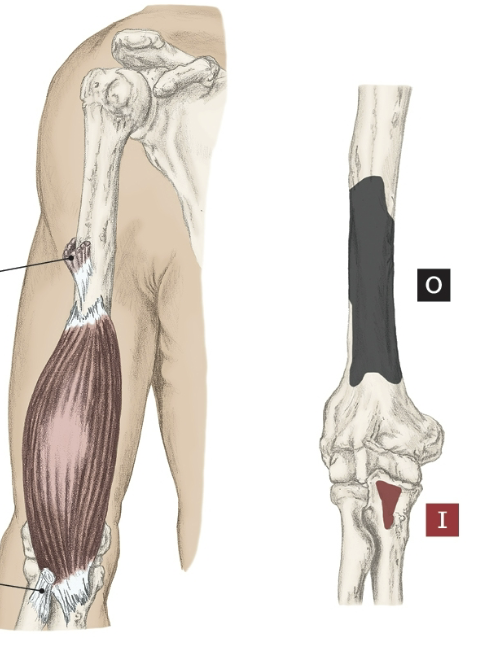

Action of the Brachialis

Elbow flexion

Origin of the Brachialis

Distal half of the anterior surface of the humerus

Insertion of the Brachialis

Coronoid process of the ulna and tuberosity.

Nerve that the Brachialis innervates

Musculocutaneous